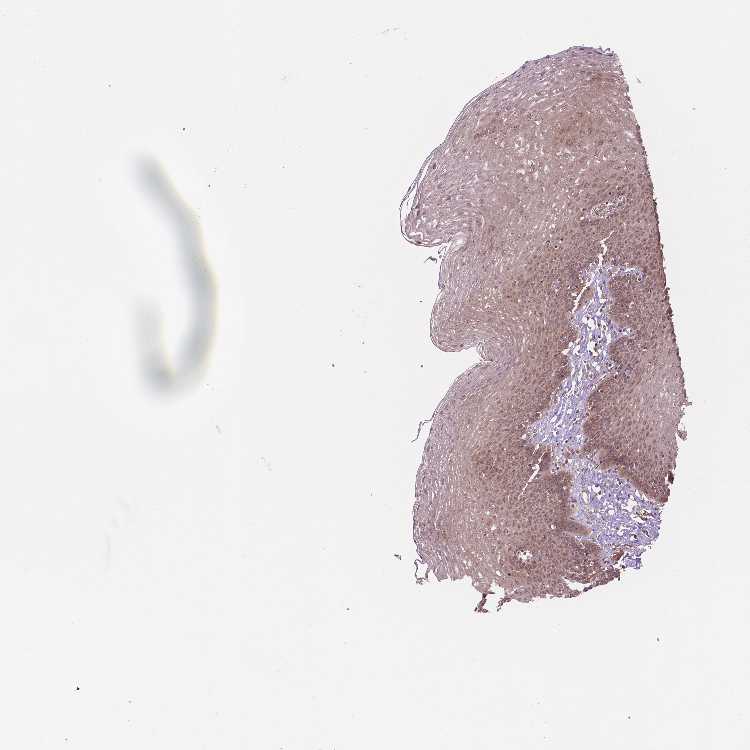

ESOPHAGUS - Antibody stainingi

Antibody staining in the annotated cell types in the current human tissue is reported as not detected, low, medium, or high, based on conventional immunohistochemistry profiling in selected tissues. This score is based on the combination of the staining intensity and fraction of stained cells.

Each image is clickable and will lead to virtual microscopy that enables deeper exploration of all samples and also displays staining intensity scores, fraction scores and subcellular localization as well as patient and tissue information for each sample.

Antibody HPA065425Antibody CAB069426

Squamous epithelial cells MediumMedium